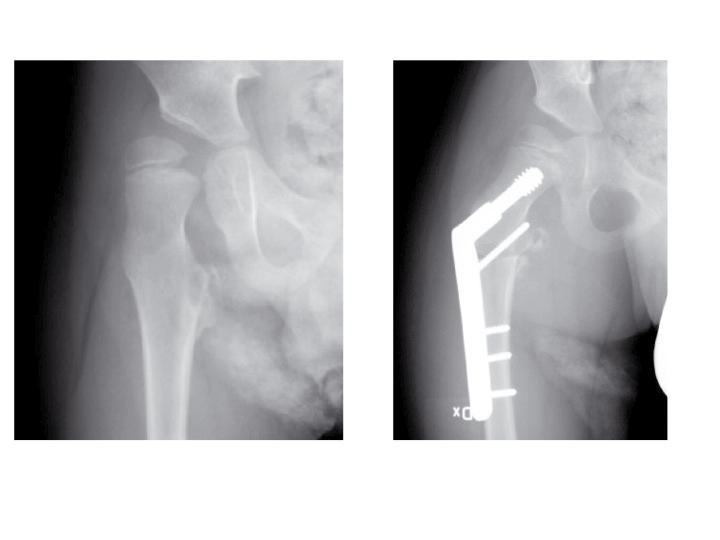

Risken att utveckla höftluxation hos barn med CP är 10-15%. Det är sedan mer än 50 år tillbaka känt att man i många fall kan förhindra uppkomsten av höftluxation med förebyggande behandling. I den förebyggande behandlingen ingår kontrakturprofylax med ortoser och bra positionering i liggande och sittande. Inte sällan krävs dessutom operation; adduktor-psoastenotomi, variserande proximal femurosteotomi och/eller bäckenosteotomi för att förhindra luxation (se Figur).

Figur 2. 5-årig pojke med CP. A. Röntgen visar lateralisering av caput i hö höft. B. Efter operation med variserande femurosteotomi.